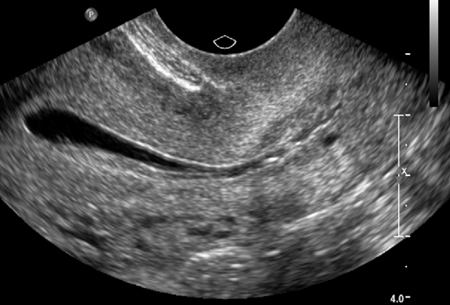

Normal hysterosalpingography (HSG)

From the collection of Dr Jared C. Robins